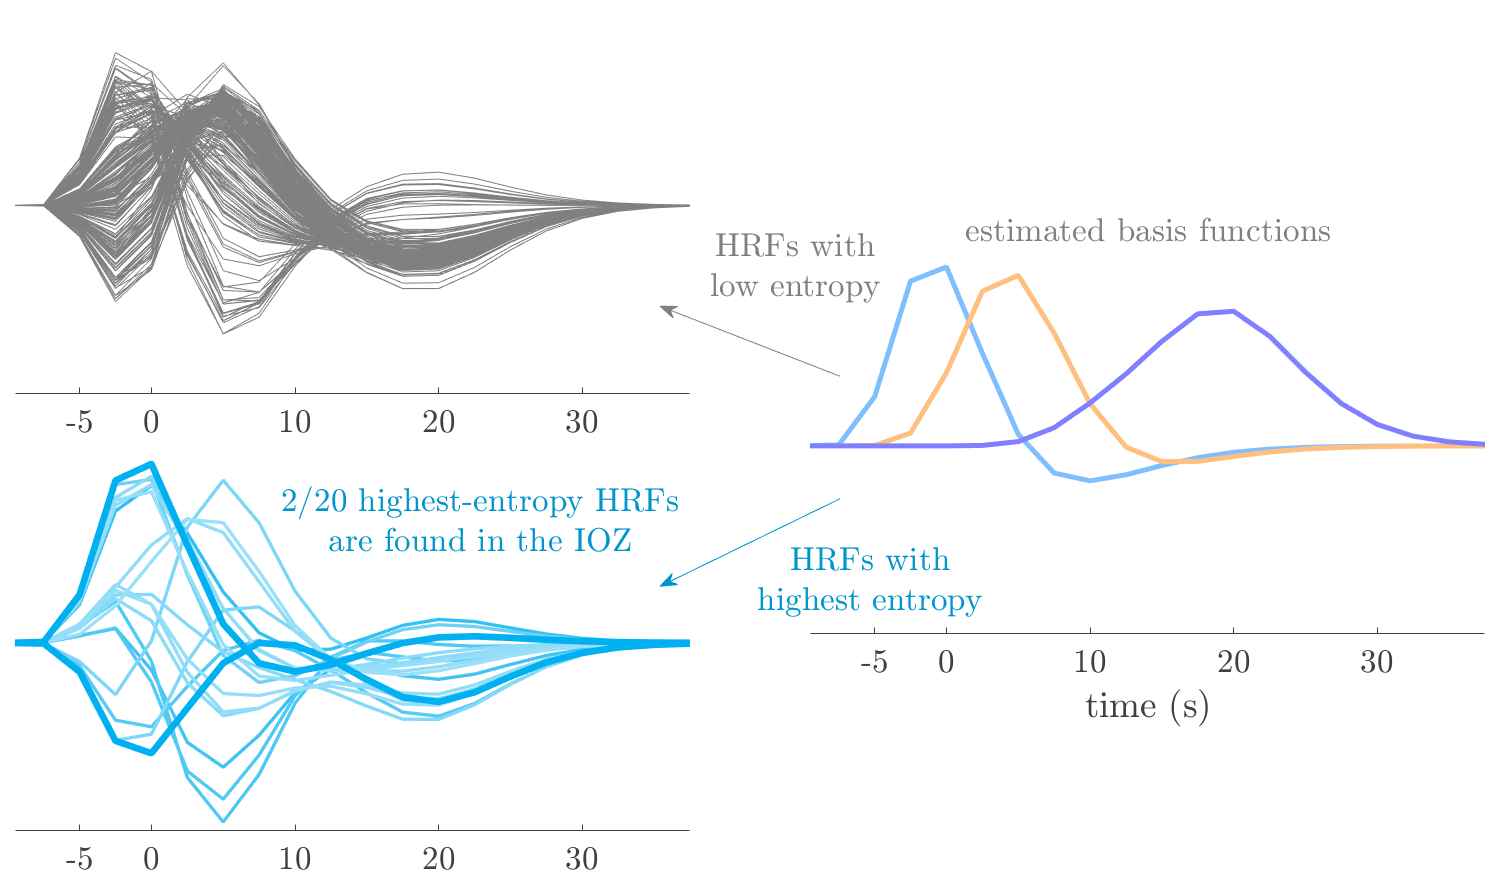

We analyze the solution with sources. Figure 1 shows the EEG signatures and HRF waveforms. One of the sources is highly correlated to the MWF reference (in grey), which was already known from Table B.3. This IED-related source had a typical low-frequency spectrum, which is expected for the typical spike-and-wave interictal discharges. The topography is relatively diffuse, although the highest amplitudes are mostly in the left hemisphere. This is in accordance with the lateralization of ictal onset zone (left temporal lobe, cfr. Table 1). There are some noteworthy observations to be made about some of the other components. The fourth has an unusually sharp spectrum, is mainly localized on two nonadjacent center electrodes, and is sustained for a single period of many seconds Hence, this component likely captured an artifact (of yet unknown origin), although we spotted no large-amplitude changes in the EEG itself. Similarly, the third source is only present at one frontal electrode, and exists in a frequency range above 20 Hz. It might represent a muscle artifact, e.g., due to frowning or twitching of some muscles in the forehead. The HRFs of all ROIs are shown in Figure 1(b). Two of the basis functions seem to have converged to a very similar waveform, which is an unfortunate possibility if two initial HRFs are too close to the same local optimum in their respective parameters. This reduces the expressive power of the basis set, which is clearly visible, since many ROIs have a nearly identical HRF. One of the twenty ROIs with the highest-entropy HRF overlapped the IOZ, although clearly this HRF (bold line) is not among the most dissimilar waveforms for this patient. This is also visible in Figure 2: both the HRF entropy and extremity maps show a small overlap with the delineated IOZ. Despite the good correspondence in the EEG domain, no significant (de)activation of the IED-component is found inside the IOZ.

We analyze the solution with sources, and show the results in Figure 3 and 4. As for patient 1, we found a source which is strongly correlated to the MWF envelope, and which had a mostly low-frequency behavior characteristic for spikes. The topography is mostly uninformative, and does not clearly correspond to the patient’s clinical data. The third source is mostly present at both sides of the head, is very sparsely active in time, and has a high-frequency content: this is most likely an artifact due to the neck muscles. Again, there is one of the highest-entropy HRFs which belongs to a ROI in the IOZ. Now, the waveform is clearly resolved from the other HRFs, through the strong initial dip (before 0 seconds). Such a dip is sometimes observed in HRFs, but its underlying physiological mechanism is not yet fully understood. It is possible that this dip reflects altered vascular autoregulation near the IOZ (cfr. the explanation in the Section 1 of the main text), or a rapid depletion in oxygen due to IED generation (before the IED becomes visible on the EEG). Figure 4 furthermore shows that the IED-related component is significantly active in parts of the IOZ, and deactive in others. As mentioned earlier, this deactivation may or may not be due to errors in sign correction. Interestingly, the ROI with the high alteration in neurovascular coupling is distinct from both the activated and deactivated ROIs.

We analyzed the solution with sources, and show the results in Figure 5 and 6. There is one source which is mostly correlated to the reference (but not extremely, see also Table B.3). This source had a right-temporal focus, conform the diagnosis in Table 1. The second source illustrates the phenomenon of an erroneous sign exchange between the spatial and spectral profiles. Also one of the HRFs has a negative polarity, which is a failure of the sign correction procedure (in this case, because there is exceptionally no positive overshoot). However, the HRF variability metrics are still interpretable, and indeed two ROIs among the ones with the highest-entropy HRFs overlap with the IOZ. The IED component is significantly active in a tiny portion of the IOZ (cfr. Figure 6). The second source is significantly active in symmetrical parts of the parietal lobe. Given its ongoing fluctuation over time, we hypothesize that this source captures a resting state network (RSN).

We analyze the solution with sources, and show the results in Figure 7 and 8. There is a clear IED-related component, with a very high correlation to the MWF reference, a typical spectrum, and an anterior-temporal focus, which corresponds very well to the patient’s diagnosis (cfr. Table 1). The fifth source seems present at only one channel, and has spectral harmonic at Hz and Hz. One of these peaks is reminiscent of the fourth component in patient 1. As Figure 8 shows, the HRF entropy and extremity prove to be strong biomarkers for the IOZ in this case, and also the significant IED activation and deactivation allow correct localization. In Figure 7, it is clear that some HRFs may still have the wrong sign, which means that the interpretation of ‘active’ and ‘deactivated’ is flipped in those ROIs. Hence, regions of significant deactivation are in fact significantly activated. The fourth source had a significant overlap with the auditory RSN, and its spectrum reveals activity in the band.

We analyze the solution with sources, and show the results in Figure 11 and 12. We found a clear IED-related component, with a characteristic spectrum and a topography which is backed up by the patient’s diagnosis (left anterior-temporal IOZ). The fourth source has a very similar topography and spectrum to the fifth source in patient 5. One HRF inside the IOZ had a high-entropy, and is distinguishable from the others by its very sluggish waveform, i.e., it is smeared out in time, with no sharp over- or undershoot. Also the pseudo t-map provided an accurate localization of the IOZ. Notably, in this patient, the extremity metric misses the deviating HRF in the IOZ (while the entropy metric picks it up). The second source overlapped with the frontal part of the default mode network (DMN), and is active in the and low bands.

We analyze the solution with sources, and show the results in Figure 15 and 16. In this patient, there is only a moderate correlation of a component with the MWF reference time course. This component’s topography (left occipital) agrees with the clinical description, however. The HRF extremity (and not the entropy) is high in a small part of the IOZ. Both the significant IED activation and deactivation allow correct localization as well. The second source seemingly captured high-frequency oscillatory activity in the sensorimotor network, similar to the previous patient.

We analyze the solution with sources, and show the results in Figure 17 and 18. The IED-related source had a high correlation with the MWF reference, but an odd bimodal spectrum. Its EEG topography is very consistent with the clinical description. Both HRF extremity and entropy are useful biomarkers for the IOZ. The IED activation and deactivation maps each had a very small overlap with the IOZ. The second source is temporally sparse and captures high-frequency EEG variations, which we identified as muscle artifacts.

We analyze the solution with sources, and show the results in Figure 19 and 20. Again we observe an IED-related source and a seemingly artifactual source with a spectral peak near 34 Hz. Many of the high-entropy HRFs are highly noncausal, and are associated to ROIs inside the IOZ. Hence, with both HRF metrics, the highest-scoring ROIs provides good localization of the HRF. While there are no significantly active ROIs in the IOZ, there are several significantly deactivated ROIs, which may indicate that the sign standardization was not done flawlessly (cfr. also some of the negative-peaking HRFs for patient 10). Surprisingly, the second source had one significantly active ROI, which overlaps with the IOZ, but which did not match its EEG topography. Hence, the nature of this source remains ambiguous.